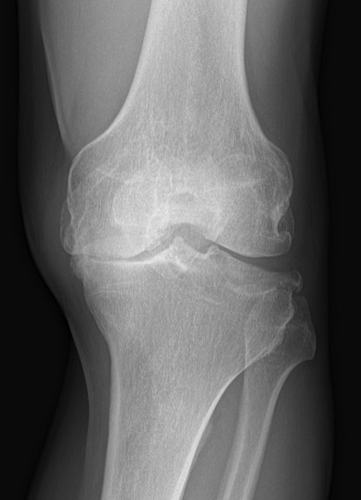

La gonarthrose consiste en une usure du cartilage au niveau du genou. C’est en général une maladie de la personne âgée. Actuellement, de plus en plus de patients jeunes et actifs sont exposés à ce type de maladie (activités sportives, anciennes opérations, etc).

La génétique, l’obésité, les défauts d’axe du membre, les instabilités chroniques, les traumatismes et les antécédents de méniscectomie sont tous des facteurs favorisant le développement de l’arthrose. En effet le ménisque est un amortisseur du genou. Sans celui-ci, l’arthrose évolue plus rapidement.

Le bilan comprend des radiographies standards en charge, une goniométrie pour mesurer l’axe mécanique.

Eventuellement un arthroscanner ou IRM afin de cartographier votre arthrose.